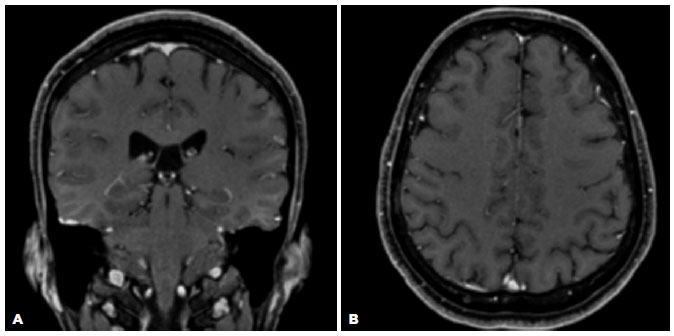

MRI revealed a lesion with impregnation by contrast in the right frontoparietal skullcap and a smooth dural enhancement along the right convexity, suggestive of an inflammatory-infectious process (Figure 2). The cerebral parenchyma and optic nerve-sheath complexes demonstrated no changes. The CSF analysis revealed negative VDRL and FTA-ABS test results, no pleocytosis (5 leukocytes/mm3), and protein levels within the reference values (36,00 mg/dL). The opening pressure was 17 cm H2O.